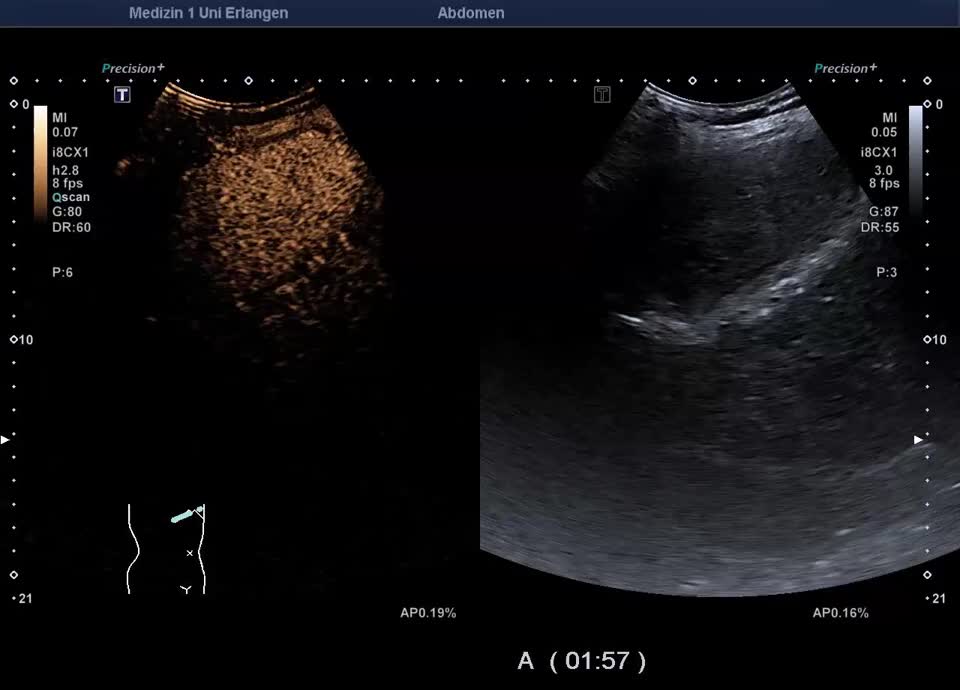

Kasuistik: 66-jähriger Patient mit seit der Jugend bekannter γ-GT-Erhöhung, sonographische Vorstellung zum Ausschluss eines cholangiozellulären Karzinoms. Sonographisch zeigt sich im B-Bild ein inhomogenes Leberparenchym mit diffus verteilten kleinen Kometenschweifartefakten im rechten Leberlappen. Das sonographische Bild ist vereinbar mit multiplen biliären Hamartomen (Von-Meyenburg Komplexe). Sie bestehen aus Zysten, die mit Gallengangsepithel ausgekleidet sind, und Bindegewebe, treten einzeln oder multipel auf und weisen typischerweise eine Größe von etwa 0,5–15 mm auf. Sonographisch stellen sie sich als echoreiche Noduli dar. Zum Ausschluss malignitätsverdächtiger Herdbefunde wurde eine kontrastmittelverstärkte Sonographie durchgeführt. Im CEUS zeigt das Leberparenchym in der portalvenösen und Spätphase homogenes Enhancement – die echoreichen Noduli sind isokontrastiert (Ausschluss Malignität). Die kleinen Zysten sind in allen Perfusionphasen nicht KM-aufnehmend. In Zusammenschau der Bildgebung und der bekannten γ-GT-Erhöhung besteht kein Anhalt für eine maligne Lebererkrankung. Eine einmalige sonographische Verlaufskontrolle wurde vereinbart.